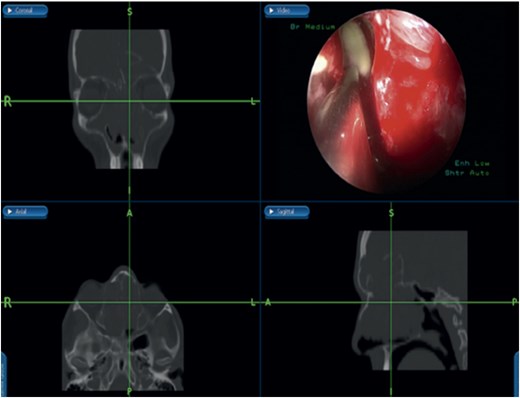

The patient underwent image-guided ESS with frontal sinusotomy. A 45-angled endoscope helped in recognition of the mucocele, which was treated with marsupialization (Fig. 5). The thick anterior inferior wall was removed. During 2 years of follow-up, no recurrence or complication was observed.

(A) Mucocele Draf IIa wide frontal sinusotomy, (B) image-guided wide marsupialization of mucocele.